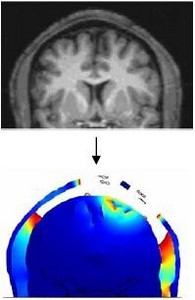

We calculated the spatial distribution of the electric fields induced in the brain during transcranial current stimulation (TCS). The spatial focality obtained using ‘concentric-ring’ configurations is investigated using a realistic MRI derived 3D finite element model of the human head. ... Mehr lesen

Electrical stimulation of the brain involves the application of currents delivered through scalp electrodes to modulate brain activity, known as Transcranial Current Stimulation (TCS). A critical factor for TCS efficacy and safety is the “spatial focality” of induced neuronal modulation. ... Mehr lesen